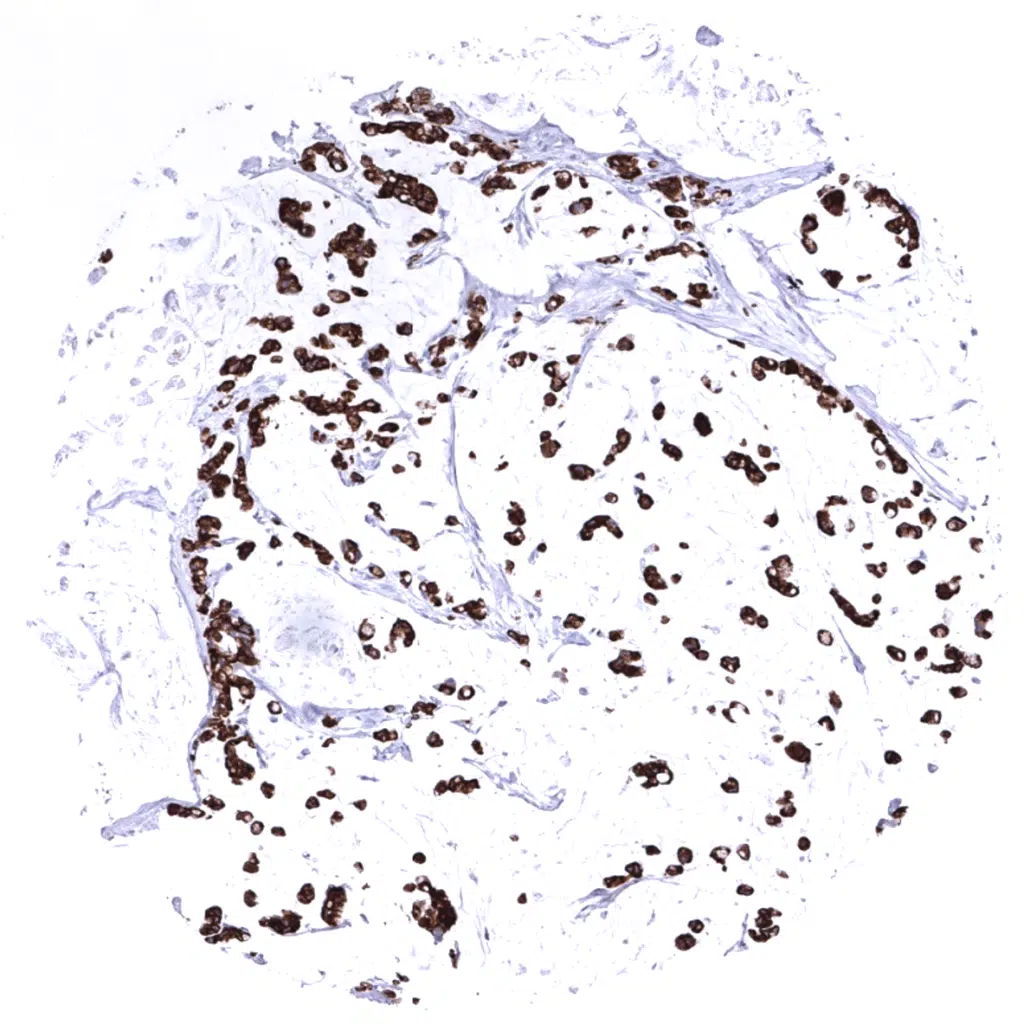

Ovary – Scattered MUC5AC positive cells in a serous high-grade carcinoma.